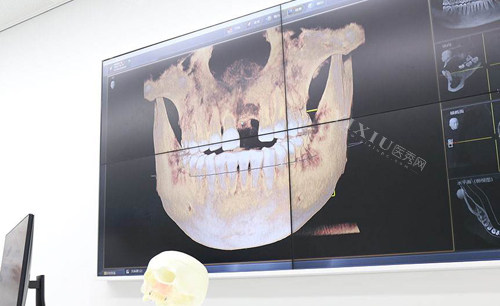

登腾种植体采用锥形设计,底部较宽,有助于增加种植体与骨组织的接触面积,提高稳定性,奥齿泰种植体则采用圆柱形设计,更适合于狭小的骨组织间隙,所以说在选择种植体方面还是要根据自身情况进行决定。

还有很多小伙伴对于多久可以做种植牙非常感兴趣,一般情况下患者需要等待一段时间,让口腔完全愈合后才能做种植牙,不过目前也有即拔即种技术,拔掉牙根之后就可以做,当然也是要看身体条件具体还是要根据自身情况进行决定。